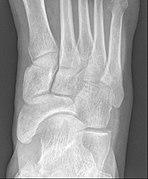

Radiological images